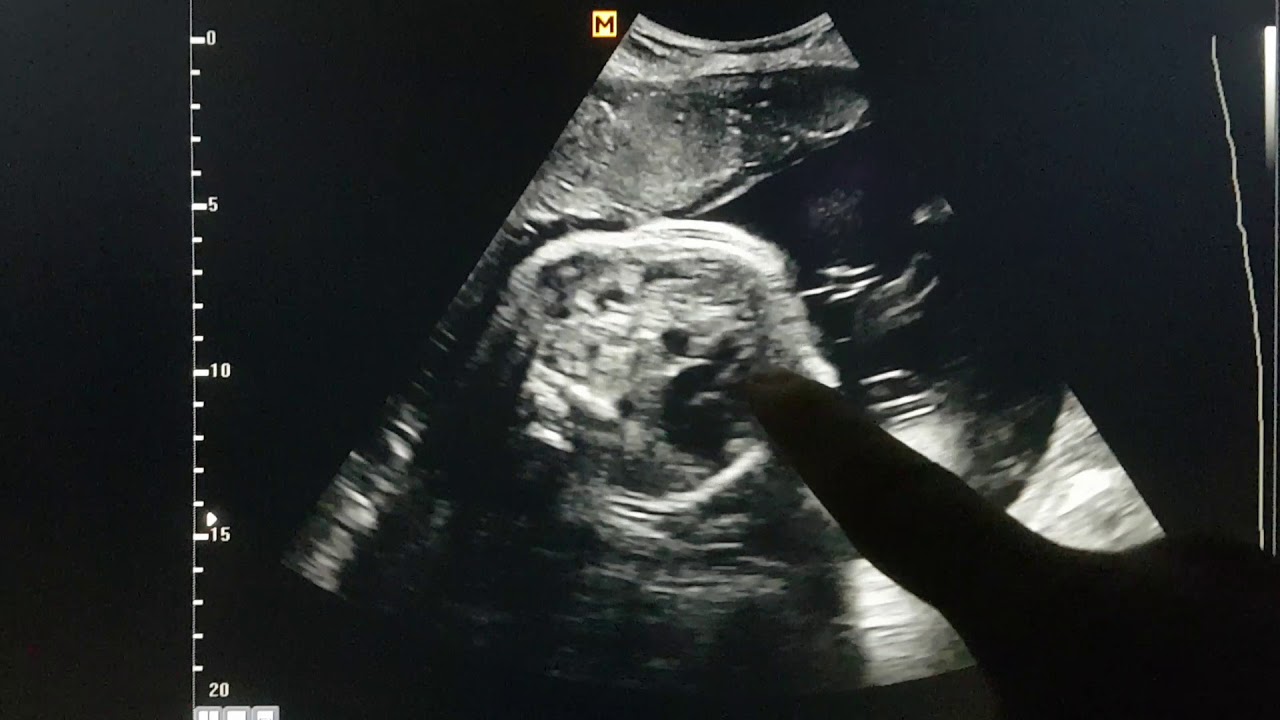

Congenital Diaphragmatic Hernia Ultrasound Diaphragm Ultrasound Baby the diaphragm is the key muscle of respiration, especially in infants. Diaphragm ultrasound is increasingly used in adults, and more recently in pediatric practice. diaphragmatic ultrasound has gained importance because of its many advantages, including the fact that it is. ultrasonography has become the modality of choice for evaluation of. ultrasound compared to other imaging modalities. Diaphragm Ultrasound Baby.

A 28week fetus with diaphragmatic hernia on the left side of the Diaphragm Ultrasound Baby the diaphragm is the key muscle of respiration, especially in infants. Diaphragm ultrasound is increasingly used in adults, and more recently in pediatric practice. ultrasonography has become the modality of choice for evaluation of. ultrasound compared to other imaging modalities to assess diaphragmatic dysfunction. diaphragmatic ultrasound has gained importance because of its many advantages, including the. Diaphragm Ultrasound Baby.